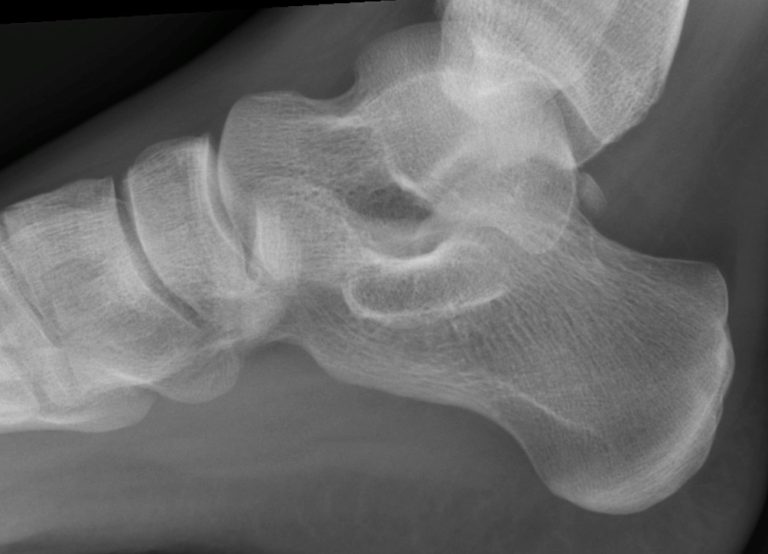

Xray of a Adults Foot